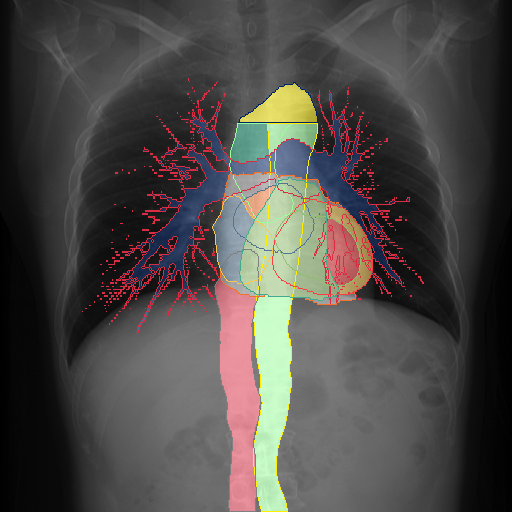

We show qualitative results for frontal projections in Fig. 2. We show a subset of classes belonging to the supercategories lungs, vascular systems, bones, and abdomen/digestive system. The predictions show minor deviations at the boundaries of the individual classes of the respiratory and vasculature system, while some inaccuracies become visible in the abdominal area. The qualitative results for the lateral projections are displayed in Fig. 2. Akin to the frontal view, the predictions show smoother borders but align with the ground truth. Apart from this, the segmentations provide matching insights on the thoracic anatomy with a slight deviation from the ground truth for both frontal and lateral views.

We display qualitative results in Fig. 3. The annotators tend to be content with most annotations. There are edits at the extensions of the esophagus, trachea, and aorta and corrections of the lower ribs. There is little consensus for classes in the abdominal area, such as the stomach, as seen on the right of Fig. 3 . In contrast, the annotators often align for bone classes.